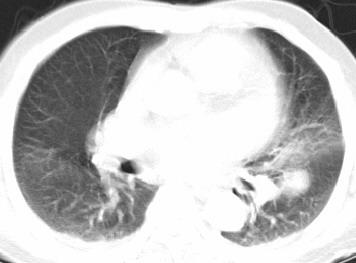

以下是引用xianxianzhongyi在2008-4-20 14:44:00的发言:[br]本人愚见:次病例短短两月的时间,呈现如此大面积实变,病变增长过于迅速,此其一。其二,病变在动脉早期既有明显强化。其三,左上叶后段及下叶背段多叶受累。其四,肺门及纵隔内未见明显肿大的淋巴结。估计层面较厚段支气管显示不清。 诊断:炎性实变可能性大。

以下是引用光影相伴在2008-4-20 14:39:00的发言:[br]支持:1)左侧中央型肺癌伴左肺上叶阻塞性肺炎。、[br] 2)双侧少量胸腔积液。